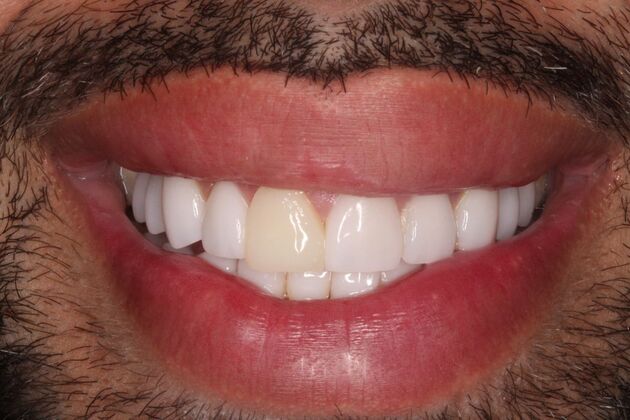

Full Mouth Rehabilitation: Eric

Description

Eric had pre-existing veneers he was wanting to have upgraded and one had recently broken while out of state. Once we consulted, we discovered Eric's bite was destructive leading to frequent headaches, popping & clicking in the jaw joints, and overall jaw fatigue. We discussed upgraded his porcelain restorations and opening his bite in order to correct his TMJ dysfunction. Treatment was completed using TENS and separated into two appointments for the top and two appointments for the bottom arch several weeks apart. Now, Eric is TMJ dysfunction free!